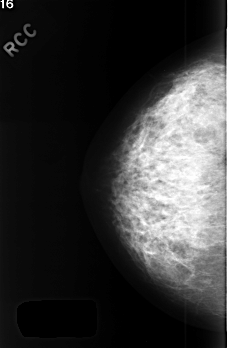

C_0412_1.RIGHT_MLO

RIGHT_CC LINES 4512 PIXELS_PER_LINE 2968 BITS_PER_PIXEL 12 RESOLUTION 50 NON_OVERLAY